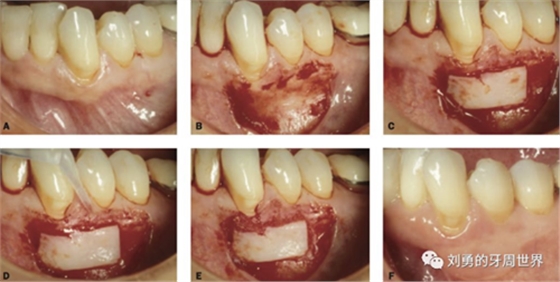

下面是上皮-結(jié)締組織聯(lián)合strip技術(shù)

如下圖:

可見右上前牙植體頰側(cè)無附著齦

為了減少取瓣大小,從上腭取厚一點的齦瓣,然后用刀片平行于表皮表面將齦瓣片切成兩個厚度一致的齦瓣,然后進(jìn)行移植,這樣切成的兩個齦瓣一個有表皮,一個沒有表皮是單純的結(jié)締組織。如此的片切可以使齦瓣變成雙倍的大小使用,減少了供區(qū)的取瓣面積。